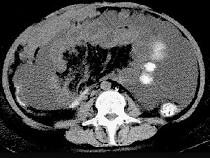

问题 男,51岁,直肠癌术后一年,腹胀,纳差,消瘦,影像检查如图,最可能的诊断是 ( )

选项 A.直肠癌肝转移 B.直肠癌网膜转移 C.肝硬化腹水 D.术后改变 E.肠梗阻

答案 B